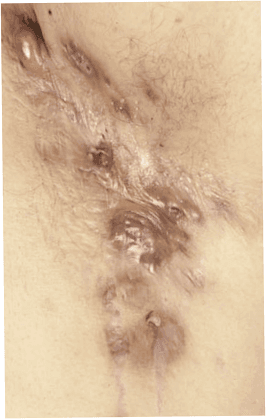

Hidradenitis suppurativa (HS)

Hidradenitis Suppurativa (HS), även känd som varbildande inflammation i svettkörtlarna, är en kronisk hudsjukdom som kännetecknas av smärtsamma knölar, sår och bölder i områden där svettkörtlar är koncentrerade, såsom armhålor, ljumskar, underliv och bröst.

Fistelgångar under huden

Ärrbildning och deformation av huden i avancerade stadier av sjukdomen